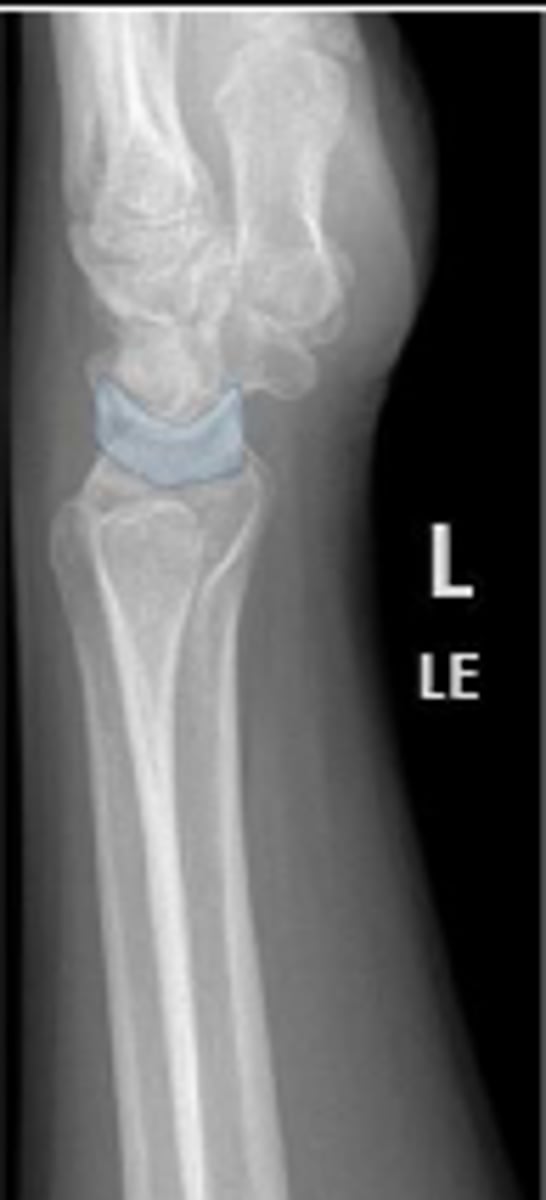

Left lateral wrist

What is the name of the radiographic view?

Left capitate

What is the arrow pointing to?

Volar margin of the left radius

Dorsal margin of the left ulna